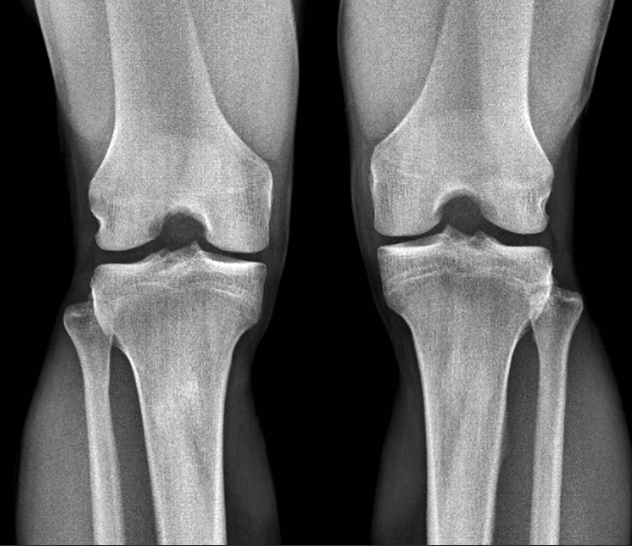

무릎 통증

이런 증상이 있다면?

계단 오르내릴 때 무릎 통증

무릎이 붓고, 가만히 있어도 아픔

오다리, 평발로 인한 반복적 무릎 손상

노화 외에도 평발, 오다리 같은 체형 문제로 인해 무릎관절이 손상되기도 합니다.

스포츠 손상도 무시할 수 없고요.

진료를 보면 50~60대 무릎 통증 환자 중 상당수가 평발이나 오다리를 가지고 있는 경우가 많습니다.

어떤 치료가 효과적일까요?

히알루론산, PRP, 줄기세포주사 등 다양한 무릎 주사치료

운동치료로 무릎 관절 안정화

봉약침으로 염증 완화

추나요법으로 무릎 정렬 개선

오다리, 평발 교정도 병행 필요